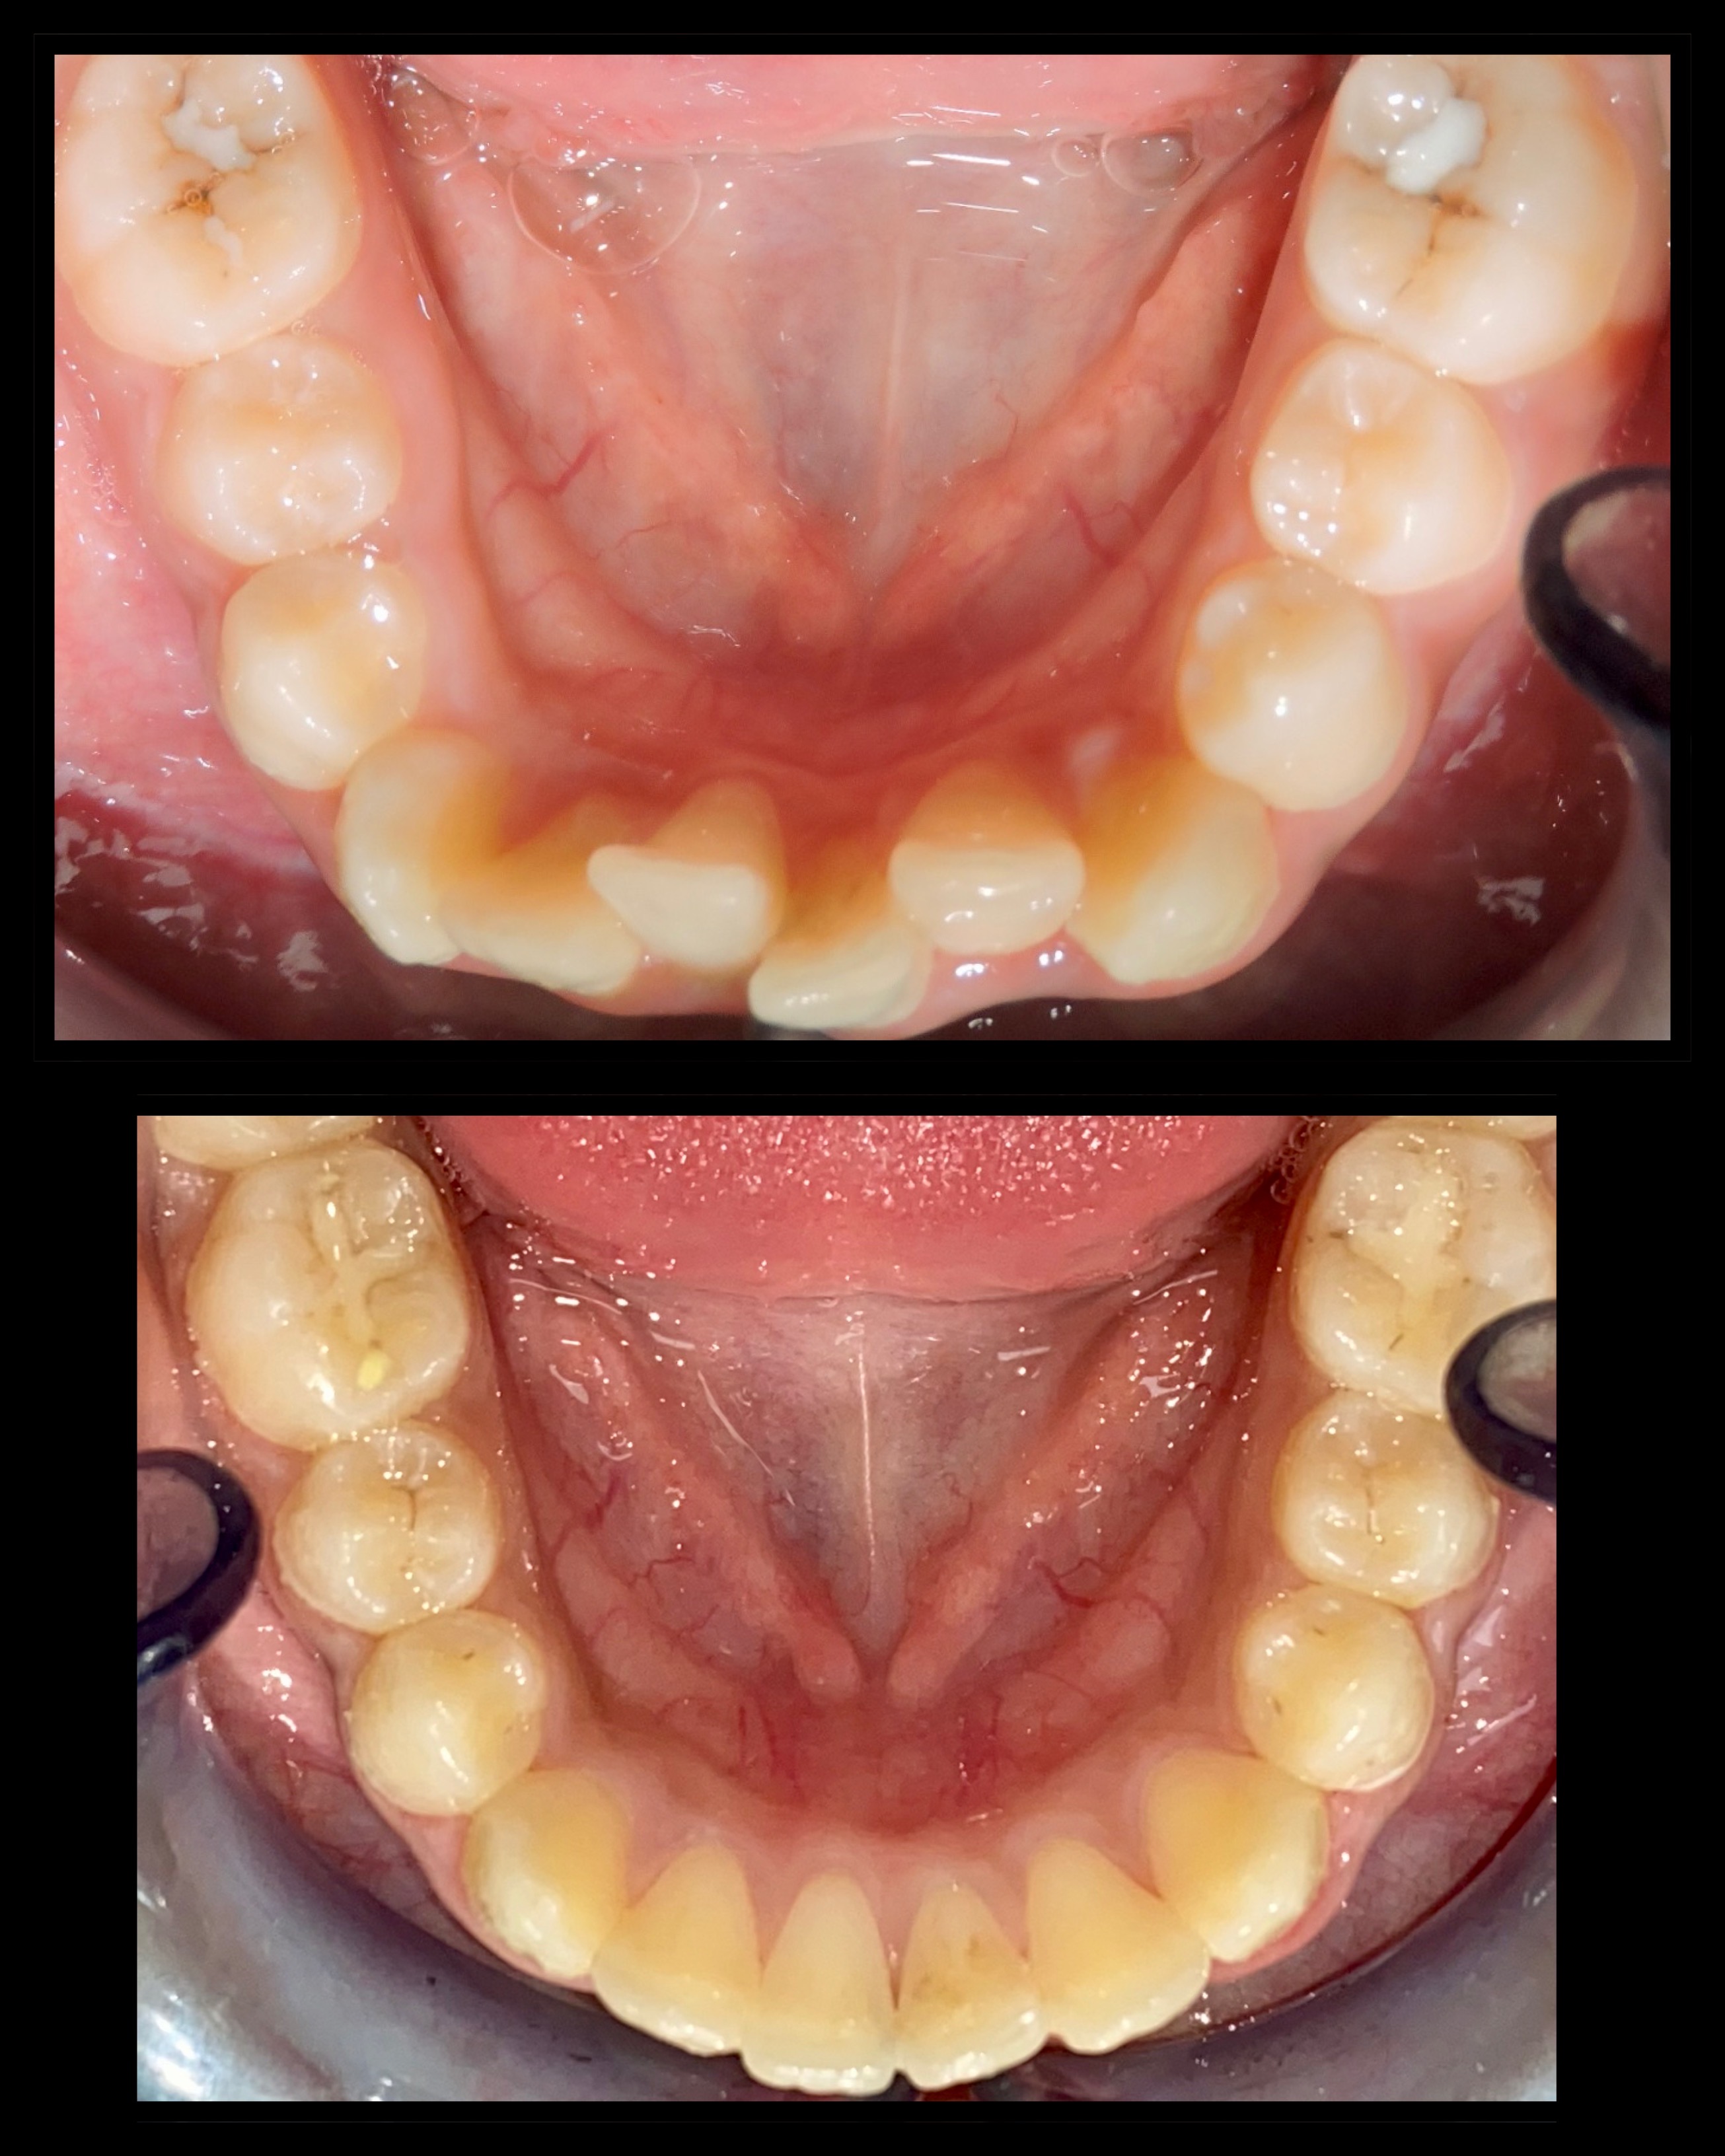

Gallery